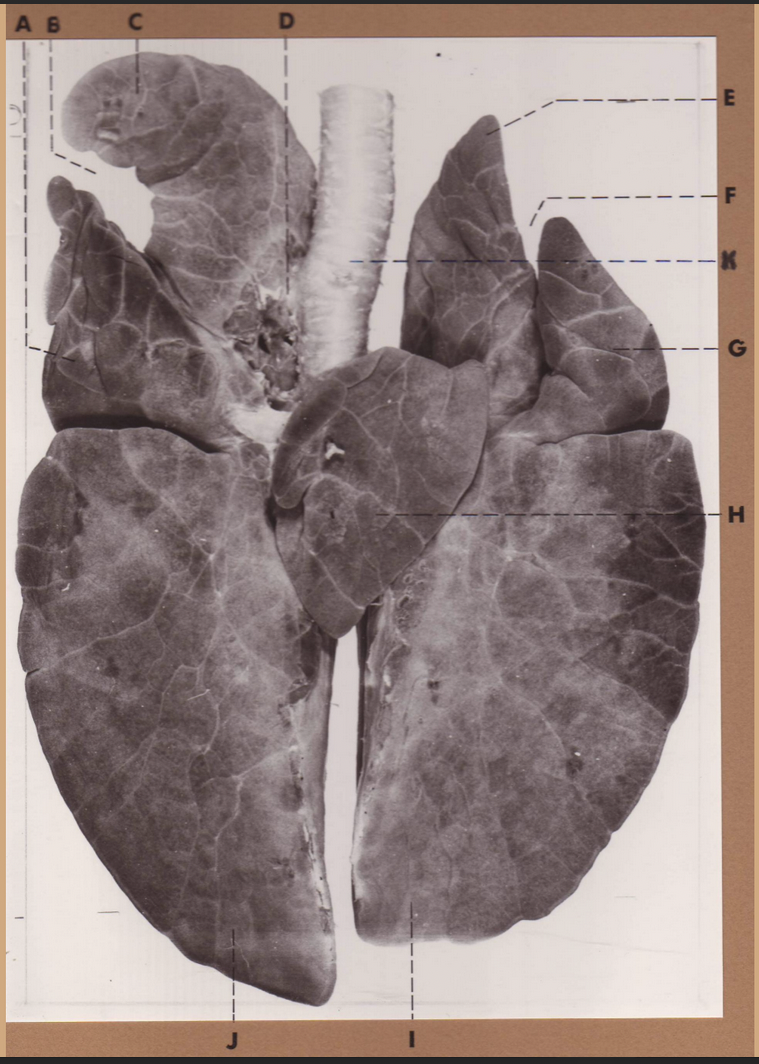

A

(pig lungs, ventral)

middle lobe

B

(pig lungs, ventral)

cardiac notch

C

(pig lungs, ventral)

R cranial lobe

D

(pig lungs, ventral)

tracheal bronchus

E

(pig lungs, ventral)

L cranial lobe, cranial segment

F

(pig lungs, ventral)

cardiac notch

K

(pig lungs, ventral)

trachea

G

(pig lungs, ventral)

L cranial lobe, cranial segment

H

(pig lungs, ventral)

accessory lobe

I

(pig lungs, ventral)

L caudal lobe

J

(pig lungs, ventral)

R caudal lobe

A

(pig lungs, ventral)

middle lobe

B

(pig lungs, ventral)

cardiac notch

C

(pig lungs, ventral)

R cranial lobe

D

(pig lungs, ventral)

tracheal bronchus

E

(pig lungs, ventral)

L cranial lobe, cranial segment

F

(pig lungs, ventral)

cardiac notch

K

(pig lungs, ventral)

trachea

G

(pig lungs, ventral)

L cranial lobe, cranial segment

H

(pig lungs, ventral)

accessory lobe

I

(pig lungs, ventral)

L caudal lobe

J

(pig lungs, ventral)

R caudal lobe